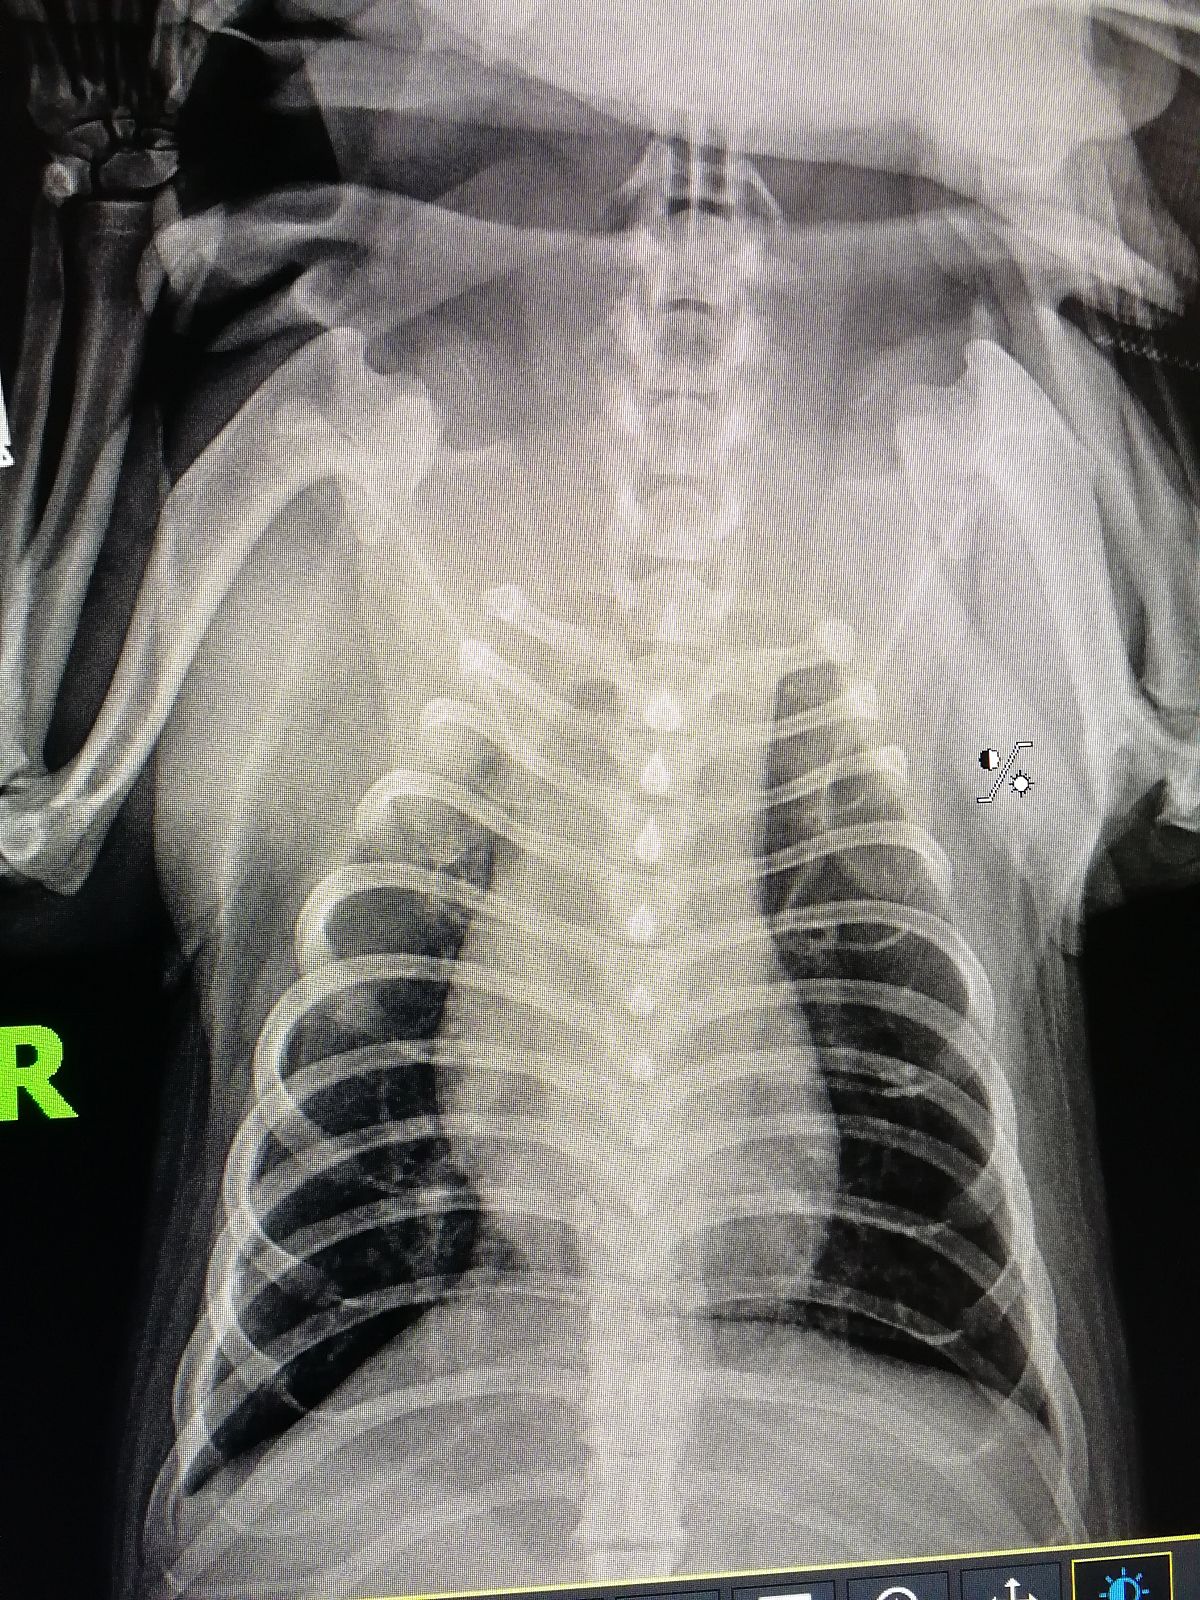

Вопрос ветеринарам по рентг. снимку собаки

Собака простужена, более 2х недель кашель. Вялый.

Подскажите, пожалуйста, на снимке Вы видете воспаление?

Сегодня сказали, что похоже на новообразование....Плачу...

цифровой в двух проэкциях